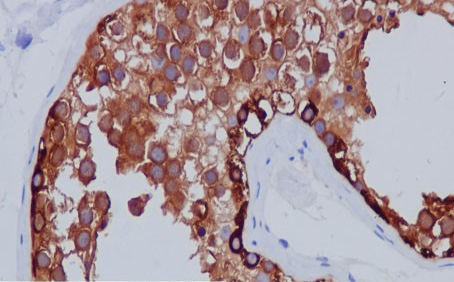

Positive control: testis

MAGE-C1 is a member of the melanoma antigen gene family. Melanoma antigens are tumor-specific and are recognized by autologous cytotoxic T lymphocytes.MAGE-C1 has been associated with diseases such as melanoma and mucosal melanoma.

The MAGE-C1 antibody reagent can specifically bind to the MAGE-C1 antigen. The immunohistochemical kit containing the MAGE-C1 antibody reagent is suitable for the precise diagnosis of multiple myeloma (MM) and certain solid tumors (such as melanoma).